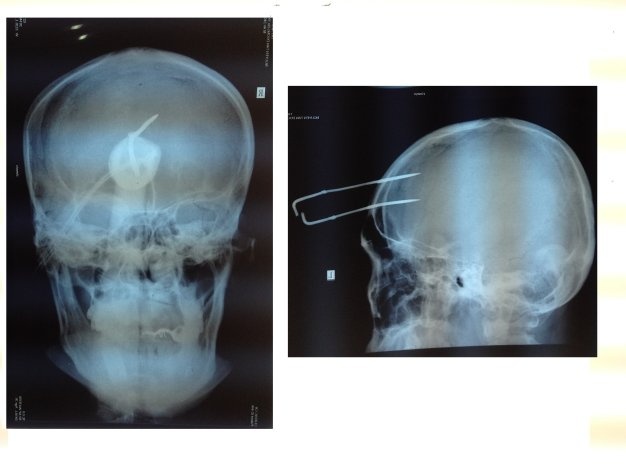

Theo chẩn đoán của bệnh viện đa khoa tỉnh Tây Ninh, bệnh nhân tỉnh táo, sinh hiệu ổn định và chụp X-quang thấy mũi chĩa ghim vào mô não sâu 5 cm. Bác sĩ bệnh viện đa khoa Tây Ninh đã quyết định mổ rút mũi chĩa ra khỏi trán bệnh nhân.

| Cây chĩa găm vào trán nạn nhân. |

Theo các bác sĩ bệnh viện Tây Ninh, mũi chĩa dài 40 cm được bắn bằng súng dạng ná bắn chĩa với đầu nối hai sợi dây điện dài.